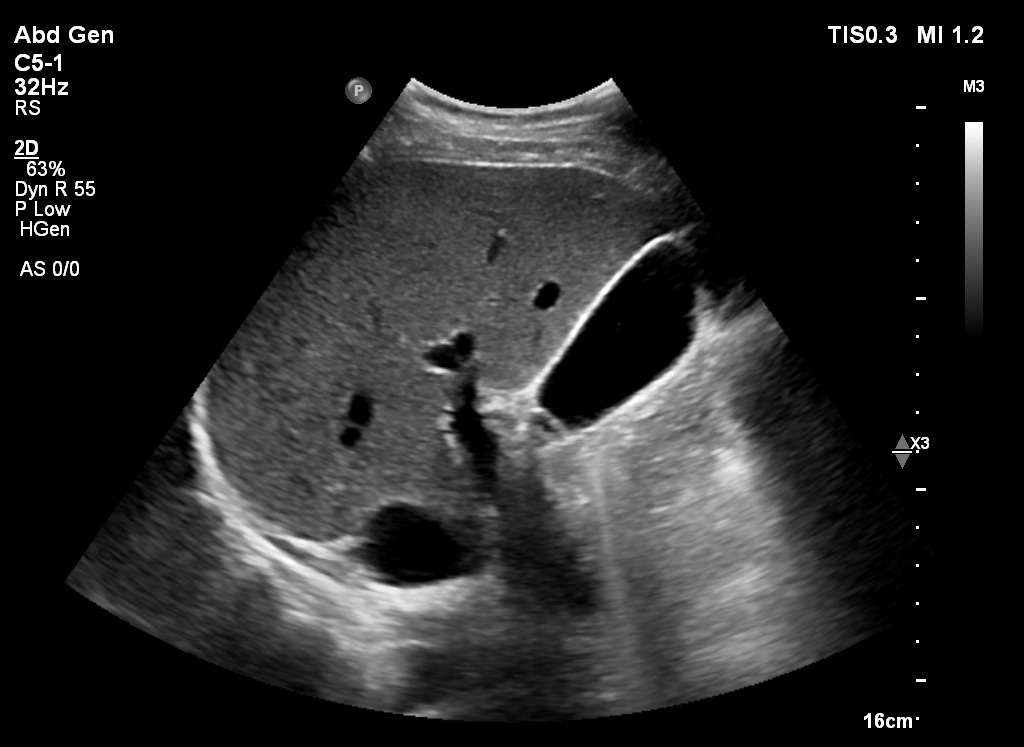

Pamje ne eko te melcise gjate ekzaminimit me ultratinguj